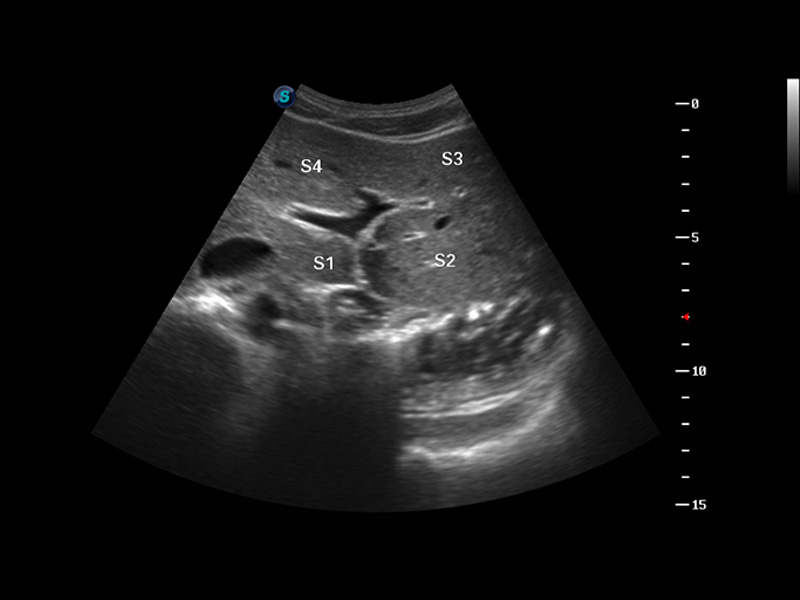

S8 EXP便携式彩色多普勒超声诊断仪是球速体育入口研发的高端全身应用型便携彩超。高通道的VIS平台融合可视化(Visual)、智能化(Intelligent)和人性化(Smart)的特点,配以球速体育入口自主研发生产的探头大家族,使您能够快速、准确的获得病人信息,提高工作效率的同时减轻疲劳。

谐波成像